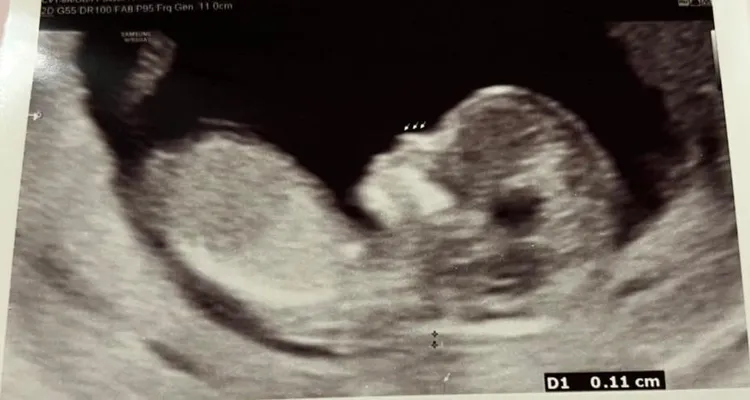

凌濤分享寶寶超音波照。翻攝凌濤臉書

凌濤今發文和大家分享喜訊,「上天給我的幸運,8年後再迎接第二個寶貝孩子」,透露今天是他36歲生日,這幾個月除了塞滿的工作外,最期待的就是每一次的產檢,看看小朋友進度,很高興他健健康康。